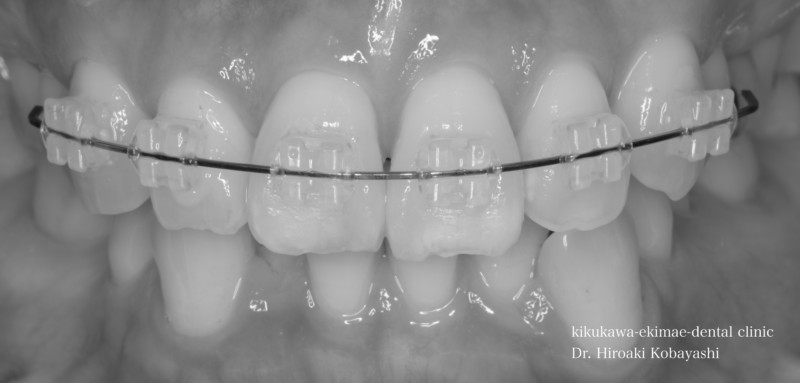

歯並びを気にされて来院されました。見た目改善を目的にワイヤーによる部分矯正を希望されました。 ブラケット装着用のマウスピースを作り、ブラケット装着を行います。   弱い力をかけながら、ワイヤーにより歯を動かします。強い力を急にかけると歯の根が吸収されてしまいます。なので弱い力で歯を動かすことによって根への負担が少なく歯根吸収のリスクが少なくなります。               6ヶ月程度で歯の並びを改善することができました。   before after